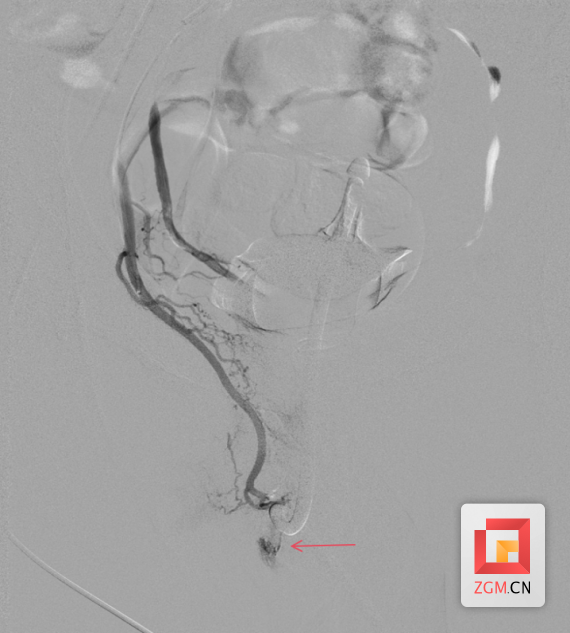

术中,介入手术中心医生在DSA(数字减影血管造影)引导下,将一根细如发丝的微导管,精准探入患者盆腔内的“犯罪血管”——阴部内动脉分支。随着造影剂的注入,屏幕上清晰地显示出了异常出血点。随即,医务人员通过微导管注入微小的栓塞材料,成功将出血点精准封堵。再次造影显示:出血信号消失,血流通畅,周围正常血管网毫发无损。